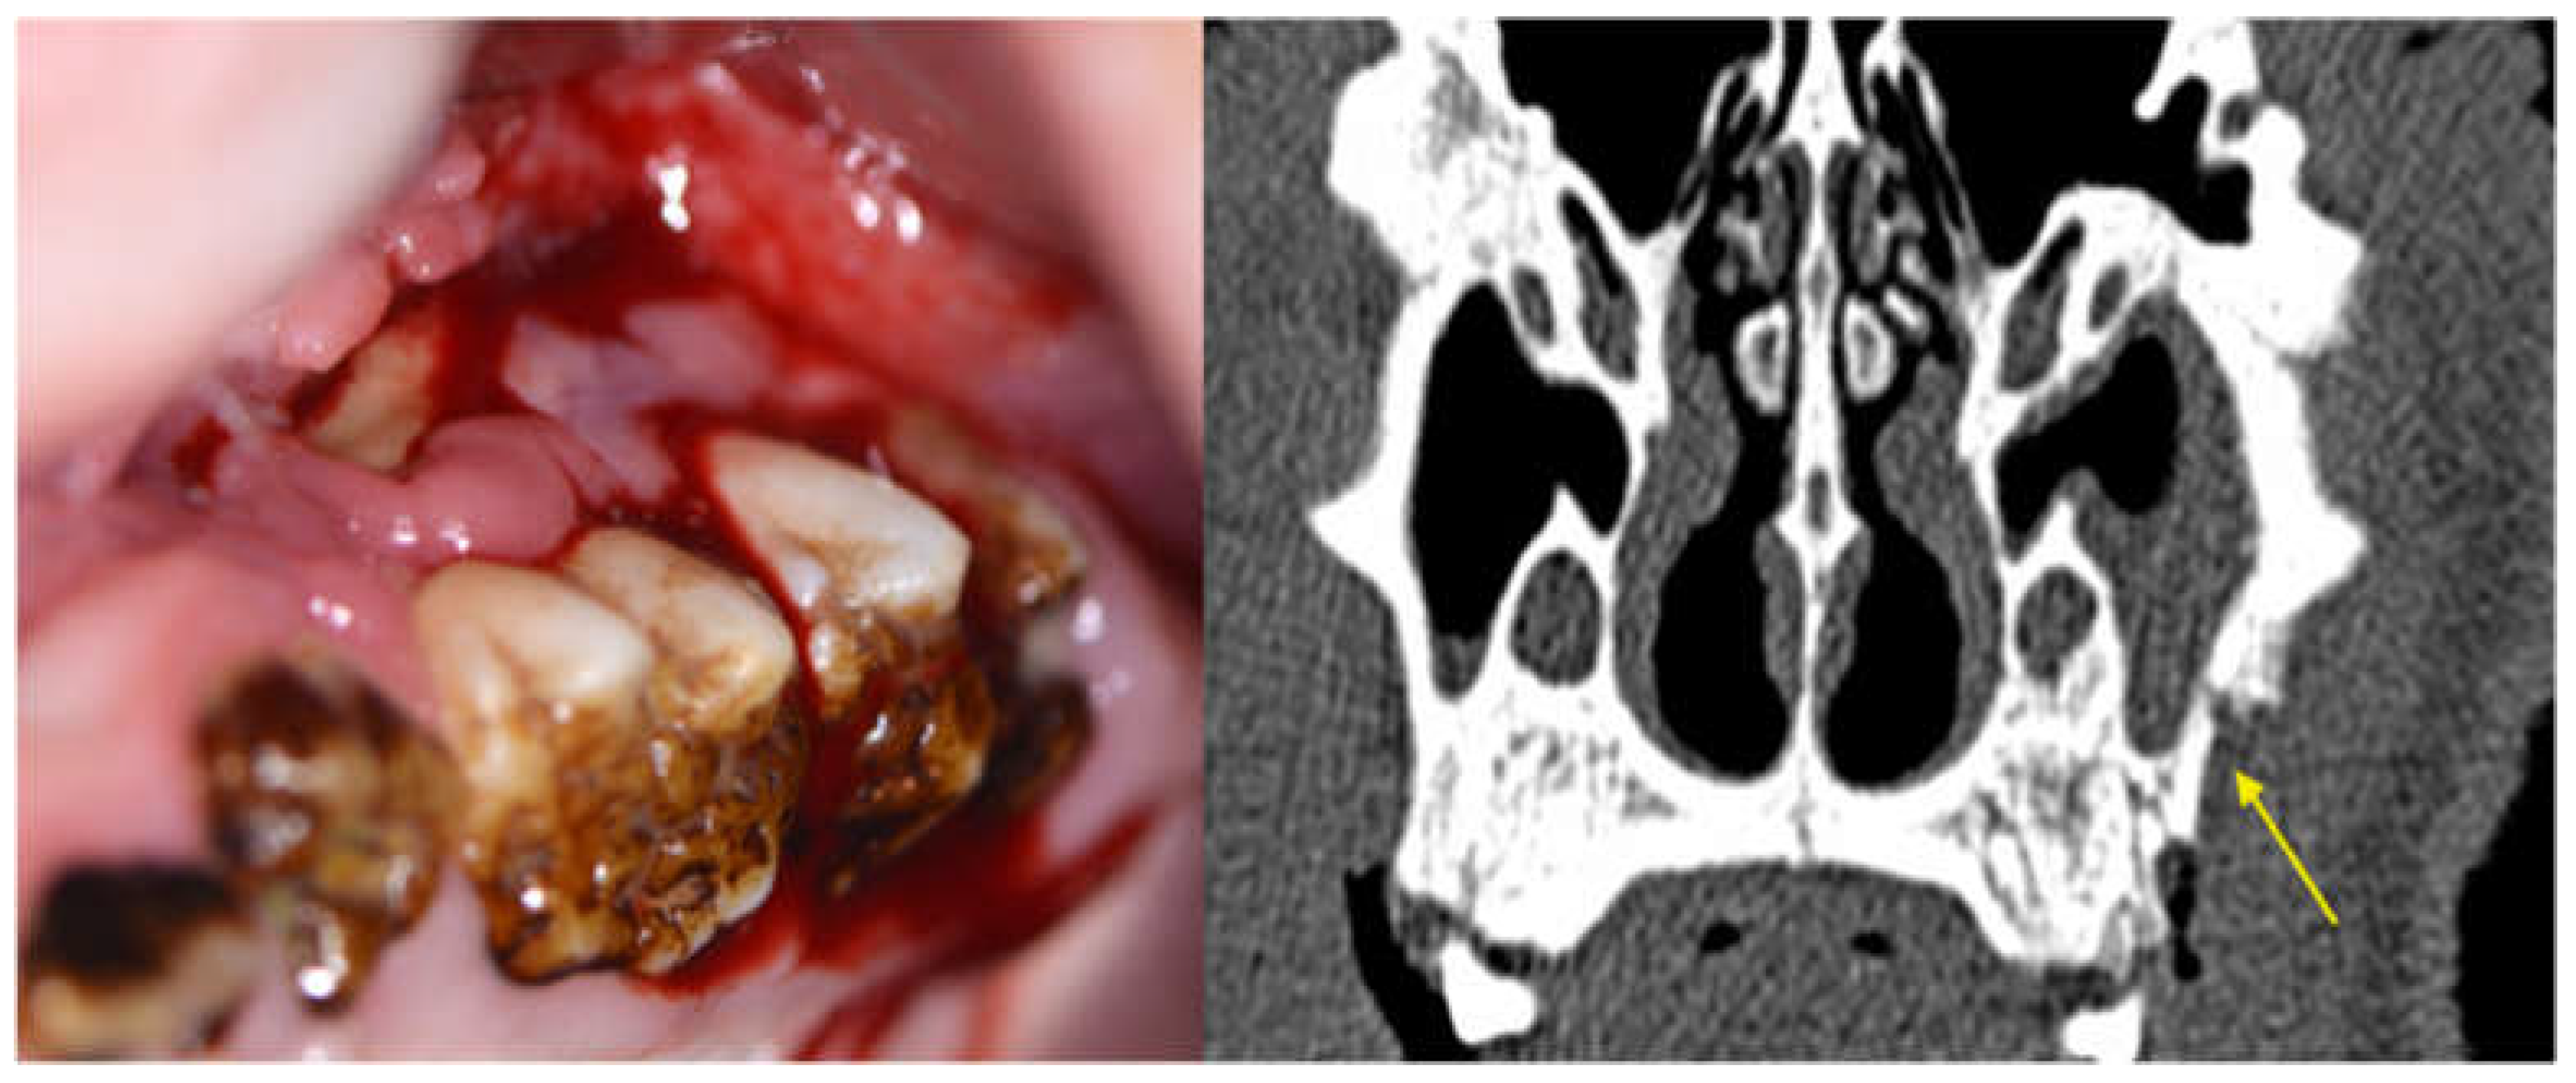

3.2.1. Clinical Evaluation

3.2.3. Radiological Evaluation